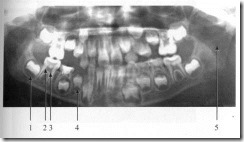

These 5 signs says you may need root canal treatment know how this treatment is done in hindi र ट क न ल ट र टम ट क ओर इश र करत ह य 5 स क त ज न क य (फाइल का प्रकार jpg)

These 5 Signs Says You May Need Root Canal Treatment Know How This Treatment Is Done In Hindi र ट क न ल ट र टम ट क ओर इश र करत ह य 5 स क त ज न क य

These 5 signs says you may need root canal treatment know how this treatment is done in hindi र ट क न ल ट र टम ट क ओर इश र करत ह य 5 स क त ज न क य (फाइल का प्रकार jpg)

These 5 Signs Says You May Need Root Canal Treatment Know How This Treatment Is Done In Hindi र ट क न ल ट र टम ट क ओर इश र करत ह य 5 स क त ज न क य